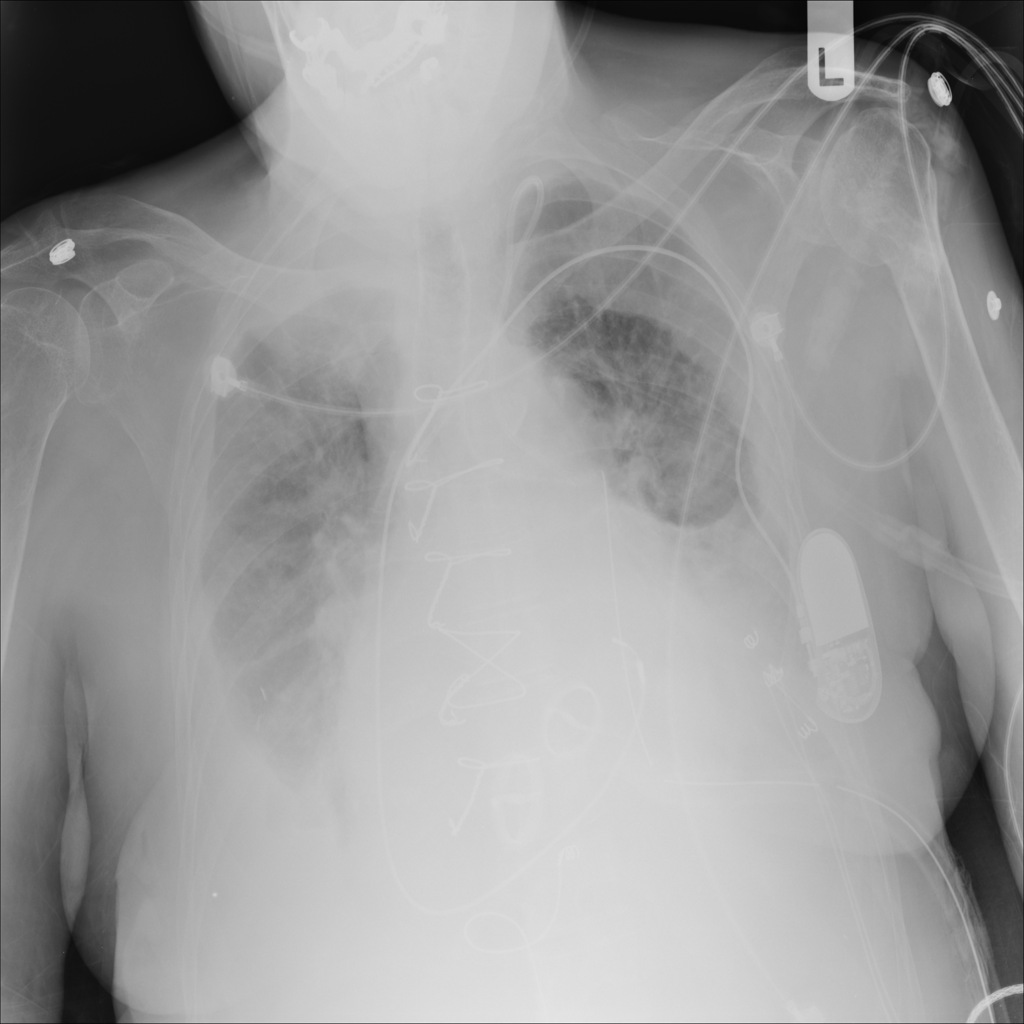

PAT-4639 · IMG-021Effusion

PAT-4639 · IMG-021

PA